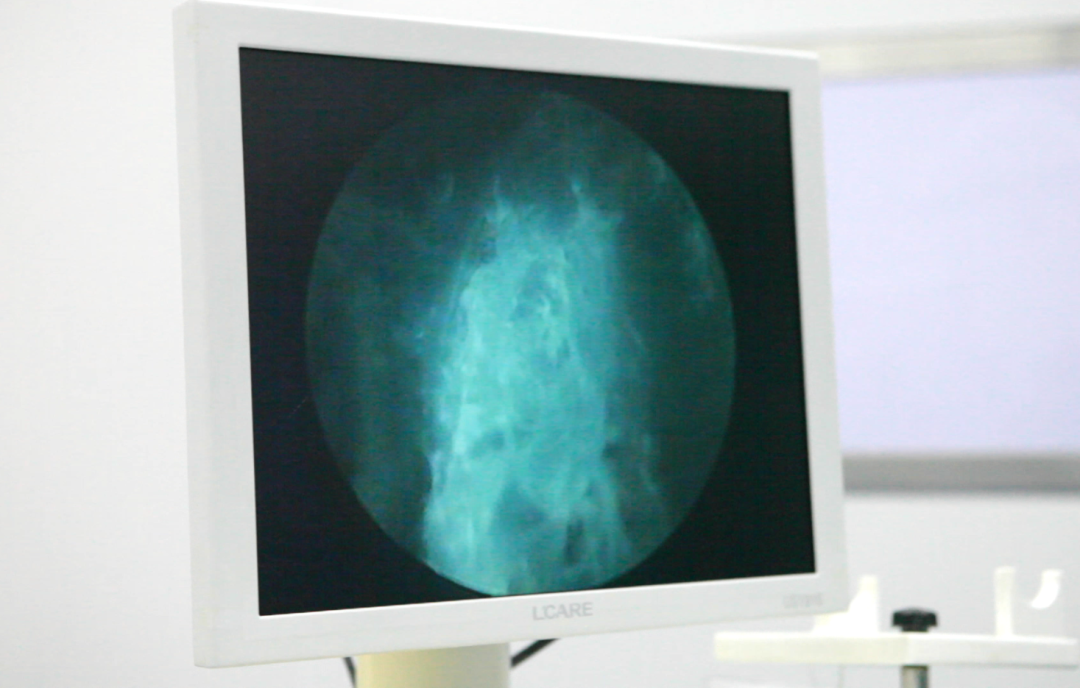

△蓝激光前列腺增生汽化术进行中

入院诊断:1.前列腺增生2.高血压1级(中危)综合外科副主任张锋刚在与刘大伯及其家属沟通后,刘大伯接受了蓝激光前列腺增生汽化术,手术非常顺利,且仅用20分钟,术中几乎无出血。术后恢复良好,留置尿管内尿色清亮,术后72小时拔出尿管,排尿通畅——手术时间短,出血少,恢复快,保留性功能,排尿问题迎刃而解,刘大伯直呼“现在小便终于利索了!”